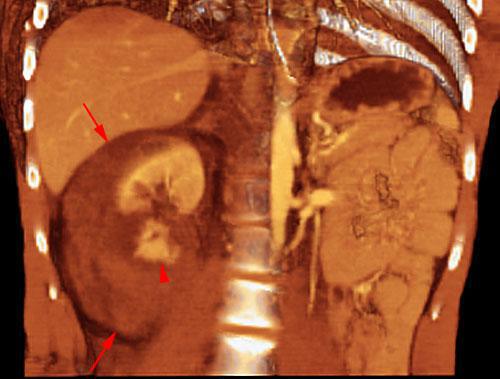

Hematoma subcapsular y perirrenal